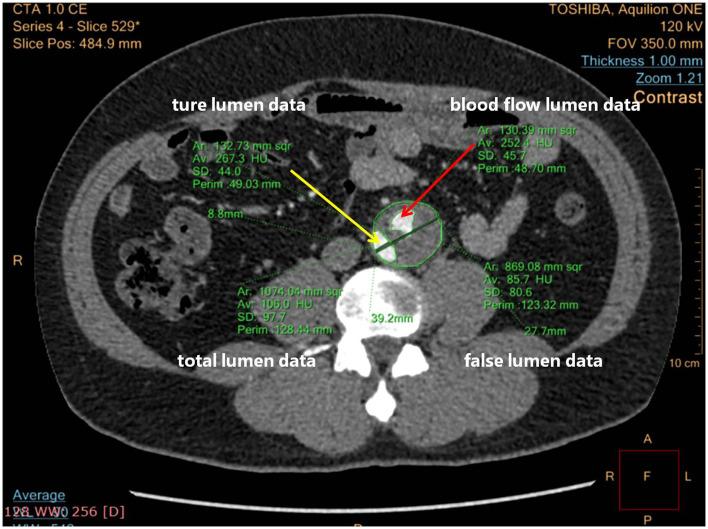

This prospective single-center clinical study included patients suffering from symptomatic distal dilatation of CADAV after aortic repair treated with RBS from January 2015 to December 2019 and followed up regularly for at least 2 years. Stent grafts were implanted first to cover distal tears and expand the true lumen. Device embolization was performed to induce proximal and distal segmental false lumen thrombosis (FLT) apart from the level of the ostia of vital branches. Successful RBS was performed in 13 patients. Significant differences were found in maximum true lumen diameter ( < 0.05), blood flow area in false lumen (FL) ( < 0.001), and the ratio of blood lumen to FL area ( < 0.05) between the pre-procedure and the latest follow-up results. No aortic rupture, vital branches occlusion, thoracic and abdominal pain, or death occurred during hospitalization and follow-up.